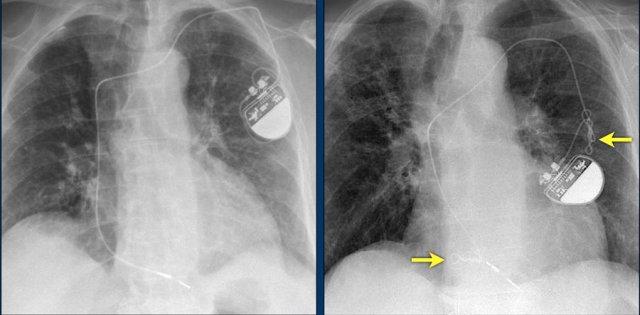

Các hình ảnh cho thấy máy tạo nhịp tim với điện cực nhĩ và điện cực thất.

Đầu điện cực nhĩ hướng lên trên và ra trước, vì vị trí lý tưởng là trong tiểu nhĩ phải, nơi điện cực được neo chặt vào các bè cơ thô.

Đầu điện cực thất được đặt tại mỏm thất phải, vị trí này nằm ở bên trái cột sống trên phim X-quang ngực thẳng và ở phía trước trên phim chụp nghiêng.

Hình ảnh được chụp ngay sau khi đặt ICD.

Có hình ảnh tràn khí màng phổi nhỏ (mũi tên).

Đây là biến chứng thường gặp nhất.

Hình ảnh bên trái cho thấy bệnh nhân có ICD được đặt đúng vị trí.

Vài tháng sau, thiết bị hoạt động không bình thường do hộp ICD và điện cực bị xoay (mũi tên vàng) và co rút lại (mũi tên trắng).